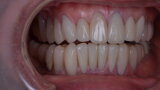

Figure 26 Closed mouth post op